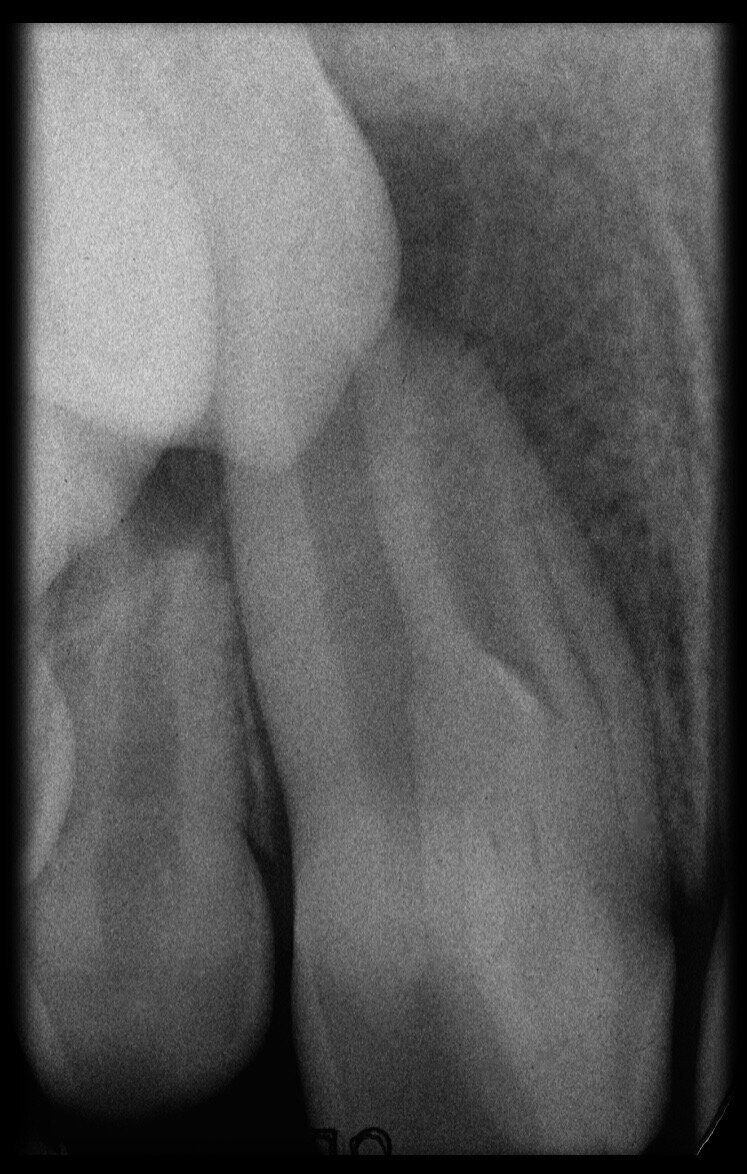

The case with which I would like to start my clinical review is a perfect example of how difficult it is to establish the origin of the patient’s symptoms on the basis of an intraoral radiograph alone. Not only does the 2D study fail to establish with certainty the presence of a lesion, but more importantly, it is impossible to establish the size, morphology and type of the lesion. An analysis of the 3D imaging, however, provides a clear picture of the clinical situation: the coronal and sagittal slices revealed the presence of a large lesion extending from the apex of the mesial root of this molar to the furcation, while the axial slices allow us to conduct a precise analysis of the endodontic anatomy and, in particular, the shape of the mesial root, which in this case was fused with the palatine root. A full overview of the case can, therefore, guide the decision-making process and direct the treatment plan towards a specific type of treatment (Figs. 1–4).